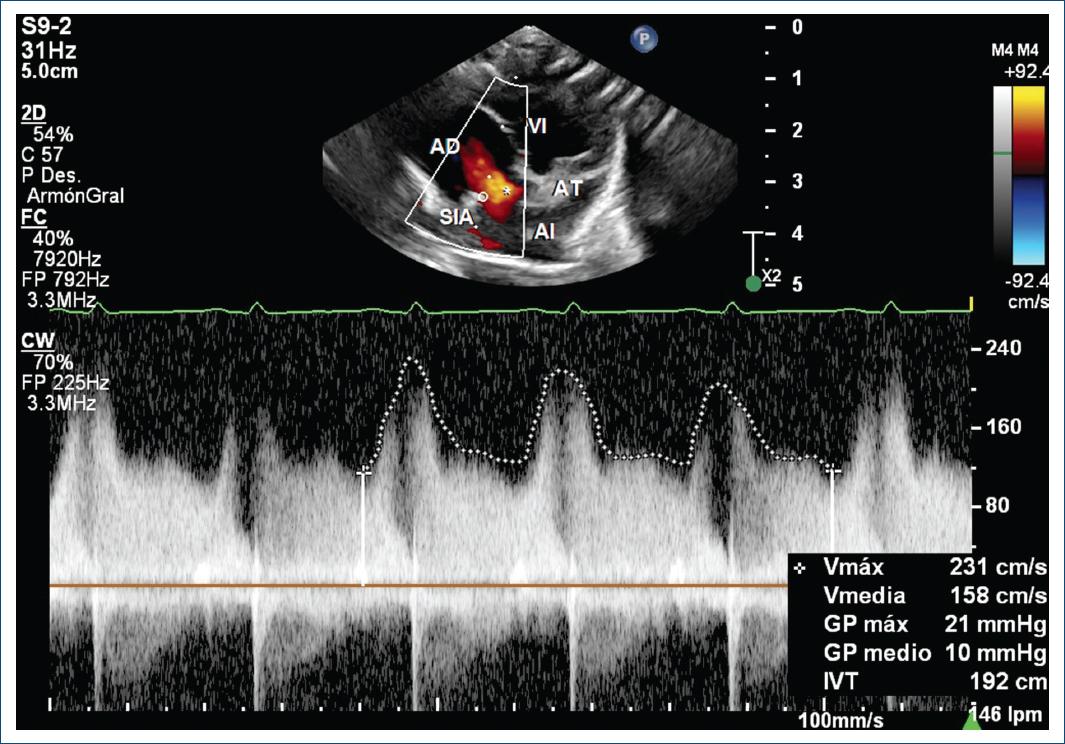

La radiografía mostró mesocardia con levoápex, con hipertensión venocapilar (Fig. 1). Se realizaron ecocardiograma transtorácico y cateterismo cardíaco, los cuales concluyen situs solitus atrial y abdominal, mesocardia con dextroápex, retornos venosos sistémicos y pulmonares lateralizados, conexión atrioventricular de tipo discordante y modo imperforado por ausencia de conexión atrioventricular izquierda, atresia tricuspídea e inversión ventricular (topología de mano izquierda) con las siguientes características: defecto interatrial pequeño y restrictivo con gradiente medio de 10 mmHg (Fig. 2); conexión ventriculoarterial tipo doble vía de salida del ventrículo derecho (rudimentario) modo perforado con aorta anterior e izquierda y doble infundíbulo, válvula pulmonar bivalva y displásica sin estenosis pulmonar; comunicación interventricular de entrada con extensión a la salida no obstructiva (Fig. 3), conducto arterioso persistente, disfunción diastólica del ventrículo sistémico y función sistólica conservada.

Figura 2 Ecocardiograma transtorácico, vista subcostal de cuatro cámaras. Se observa un defecto interatrial (asterisco) restrictivo con gradiente medio de 10 mmHg. AD: atrio derecho; AI: atrio izquierdo; AT: atresia tricuspídea; SIA: septo interatrial; VI: ventrículo izquierdo (video para imagen 1: https://youtu.be/U4n-y8YUbwo).